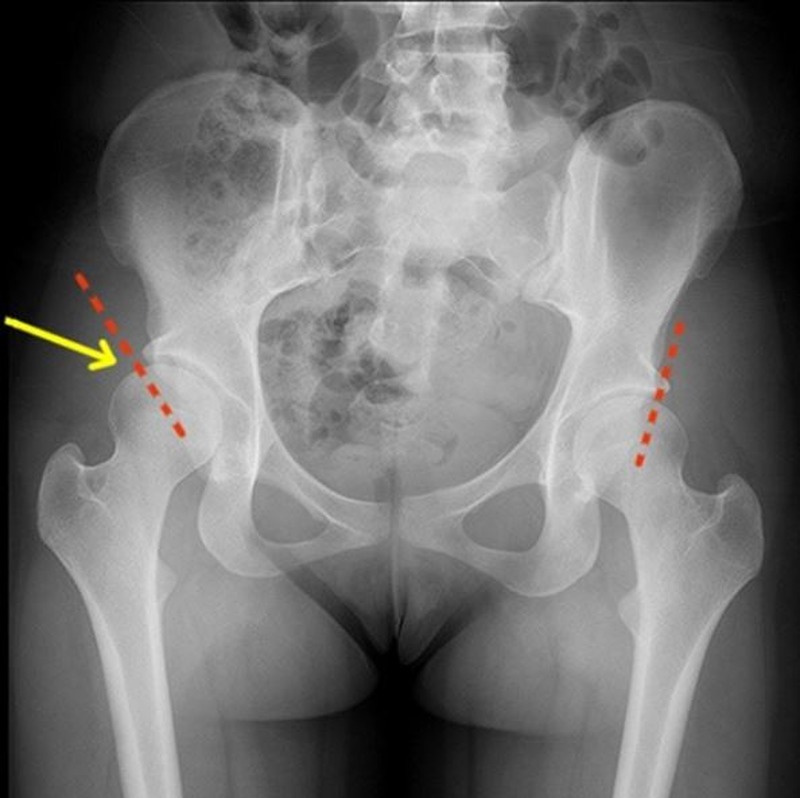

Рентгеновские снимки: Синовит тазобедренного сустава